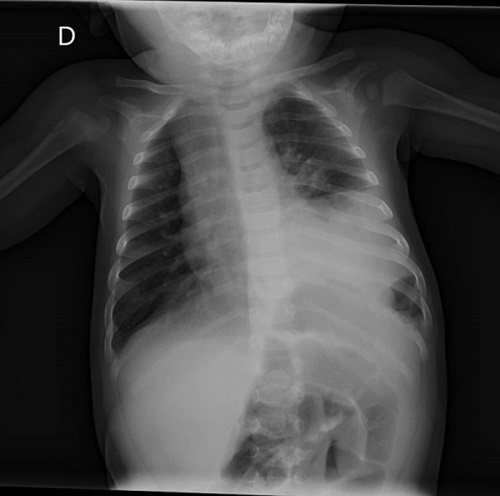

Se completa el estudio con una analítica, sin alteraciones, y una radiografía de tórax (Fig. 2) informada como consolidación basal izquierda sin poder descartar derrame pleural, motivo por el cual se decide realizar ecografía torácica donde se observa una imagen compatible con una hernia diafragmática congénita izquierda (Fig. 3).

| Figura 3. Hernia diafragmática congénita de presentación tardía (paciente de 6 meses). En la ecografía torácica: localización: pared costal izquierda, por encima de la mamila; se observa asas intestinales (círculo amarillo) |

Nuestro paciente presentó un cuadro de llanto persistente en posible relación con dolor abdominal, llegándose al diagnóstico tras la realización de una radiografía de tórax con una imagen sospechosa que se confirmó en la ecografía torácica. Dada su estabilidad clínica y a que luego permaneció asintomático, se prefirió completar el estudio diagnóstico previo a la realización de la cirugía. Nuestro caso, refleja la amplia variedad de manifestaciones clínicas de la HDC y la dificultad en su diagnóstico en los casos asintomáticos o poco sintomáticos.